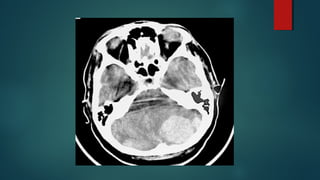

Este documento es el programa para un taller de imágenes del curso de emergencia 2015 impartido por el Dr. Víctor Delgado. El taller se centra en el uso de imágenes médicas para el diagnóstico y tratamiento de pacientes en coma traumático según la base de datos de Marshall. El Dr. Delgado es el único instructor repetido a lo largo del documento.